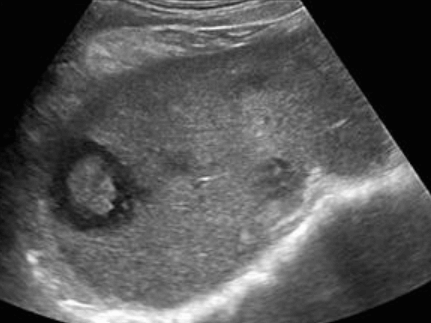

US finding

- 동일한 크기의 다발성 종괴가 나타난다.

- 고에코의 다발성 종괴: 대장암이 많으나 위암도 비교적 흔하다.

- 저에코의 다발성 종괴: 유방암, 폐암등에서 나타난다.

- 석회화나 내부 낭성 변성은 전이성 간종양을 시사하는 소견이다.

- bull's eys sign (종양 변연에 중심부가 고에코이고 경계부가 저에코인 두꺼운 띠가 보인다)

- cluster sign (종양이 융합하여 분엽모양을 이루어 마치 포도송이 모양을 나타낸다)